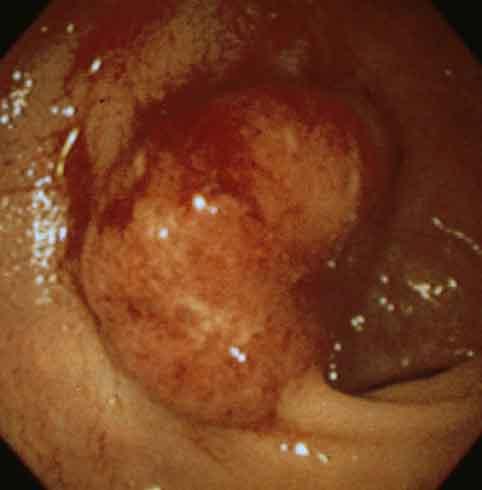

질환(병리주체)의 분류 악성 상피성종양/선암

부위(장기별) 대장/S상

검사방법 내시경

종양의 육안분류 1형(종괴형)/

종양의 최대경(밀리미터) 30~34

종양의 심달도 s(a)